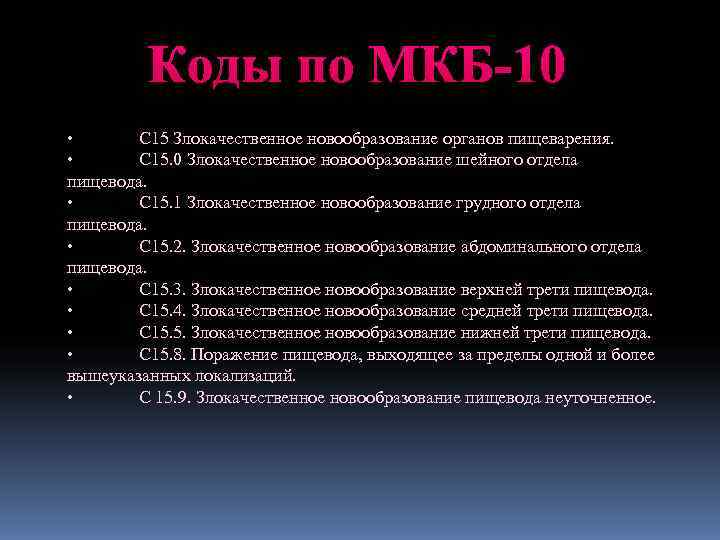

Код мкб 10 атерома головы

Код мкб 10 атерома головы 109 фото